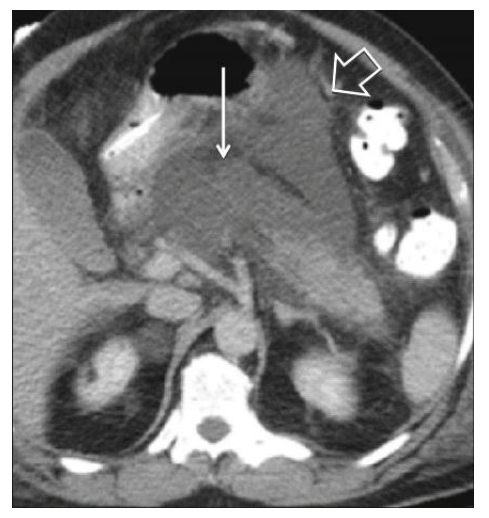

Classificação Tomográfica de Balthazar

Gradua a inflamação e necrose:

- A: Pâncreas normal.

- B: Aumento focal ou difuso.

- C: Inflamação peripancreática (densificação da gordura).

- D: Uma coleção líquida.

- E: Duas ou mais coleções ou presença de gás.

Complicações Locais: A Linha do Tempo

A nomenclatura correta depende do tempo e do conteúdo (líquido ou sólido/necrose).

| Tempo | Conteúdo Líquido (Homogêneo) | Conteúdo Sólido (Necrose/Heterogêneo) |

| < 4 Semanas | Coleção Peripancreática Aguda | Coleção Necrótica Aguda |

| > 4 Semanas | Pseudocisto (tem cápsula) | Walled-off Necrosis (WON) (Necrose encapsulada) |